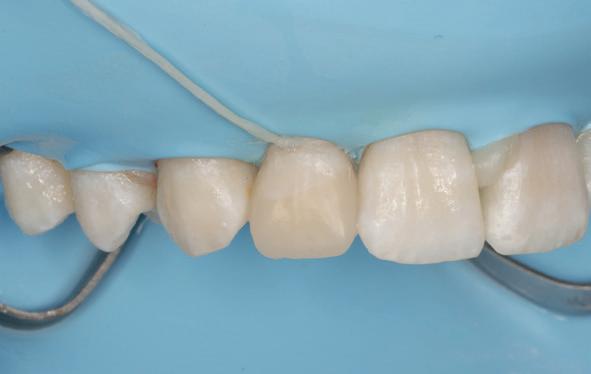

De kanalen zijn ultrasoon gespoeld met 2% NaOCl en EDTA onder isolatie van rubberdam. Het kanaal van de 13 is gevuld met MTA (afbeelding 8), omdat er sprake was van een niet-afgevormde radix. Dit is afgedekt met een laagje Vitrebond. In de 12 en 11 hebben we guttapercha en AH26 aangebracht via een hybride vultechniek (afbeelding 9).

Er is een plastische opbouw vervaardigd van het composiet opbouwmateriaal Clearfil core, dat diep is verankerd in het kanaal. Er is een definitieve restauratie vervaardigd van composietmateriaal Filtek Z250 kleur A3 (afbeelding 10 en 11). De behandeling is technisch goed verlopen. Echter, we hebben hem en zijn moeder uitgelegd dat de prognose

van de 13 voor de lange termijn dubieus was.

Behandeling 42, 41, 31

Na het verwijderen van de lekkende glasionomeerspalk, lagen alle pulpae bloot. De 42 was bovendien verticaal gefractureerd (afbeelding 12 en 13). Het topje van de pulpae van de 31 en 41 kon worden verwijderd, en na spoelen met NaOCl persisteerden twee vitale pulpae, die zijn afgedekt met een laagje Vitrebond (afbeelding 14).

Daarna zijn de tanden weer opgebouwd met een composietrestauratie van Filtek Z250 kleur A3. De 42 is tijdelijk afgesloten met glasionomeercement, met het verzoek aan de tandarts deze tand te extraheren.